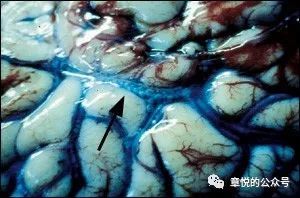

图4. 这是一个大脑,蓝色的是脑表面的静脉血管,血管里可看到一个个气泡。这是尸检,说明减压病真会死人!